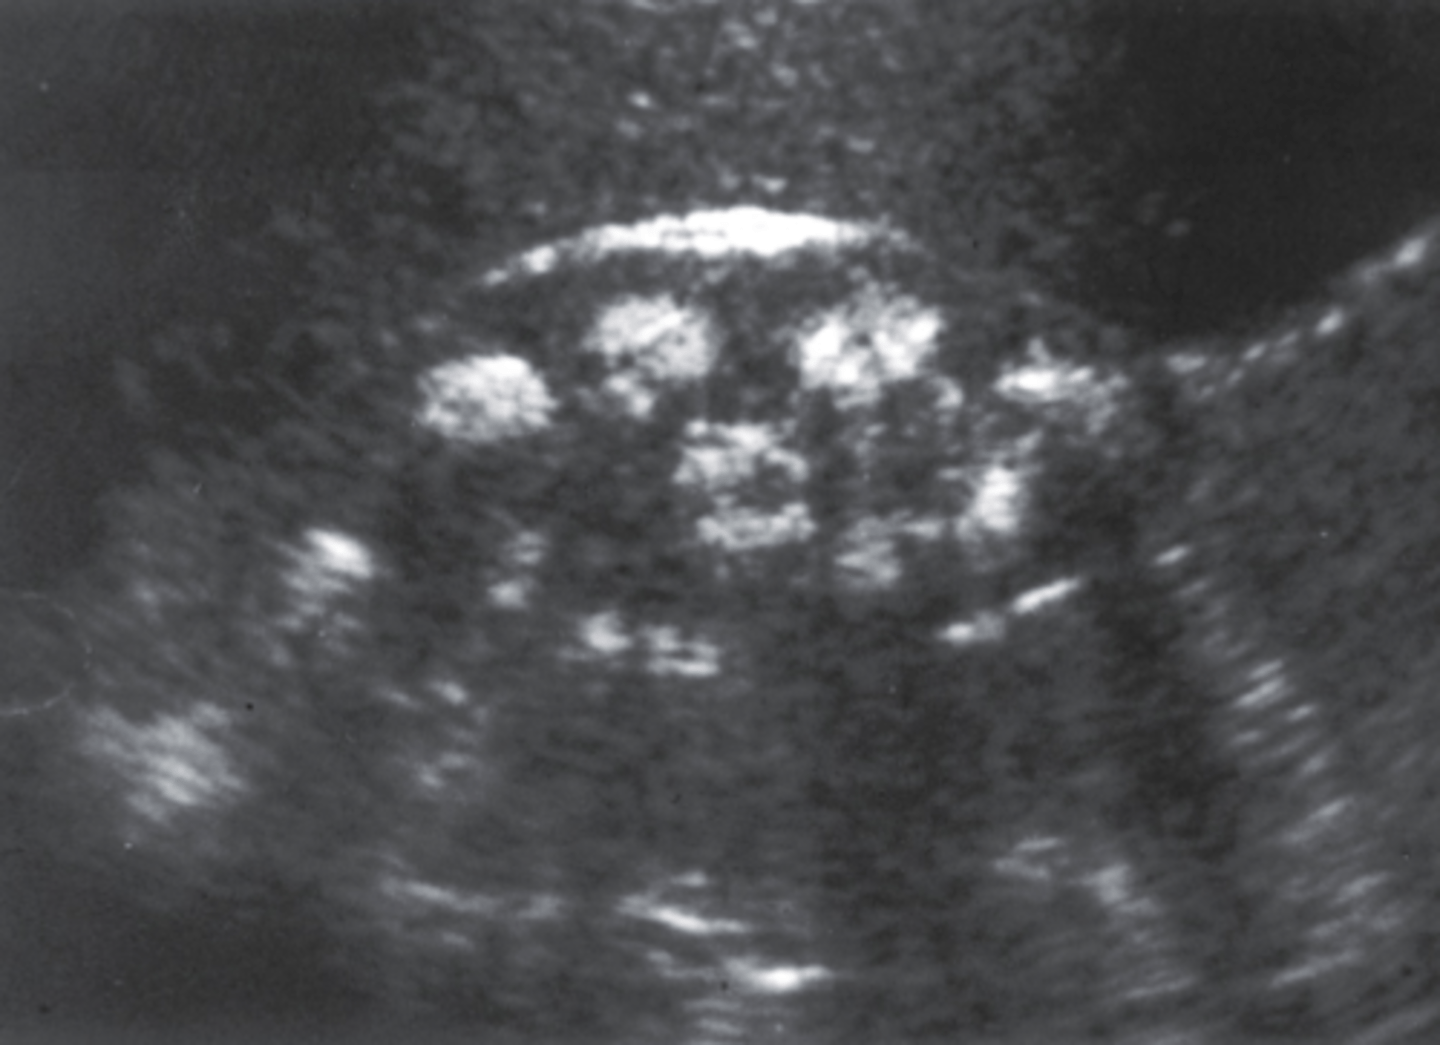

11. What are the sonographic findings in Figure 7-44 consistent with?

a. Multiple renal hemangiomas

b. Medullary nephrocalcinosis

c. Renal lipomatosis

d. Schistosomiasis

12. Which of the following would be least likely associated with Figure 7-44?

a. Pyonephritis

b. Hypercalcemia

c. Urinary tract infection

d. Hyperparathyroidism